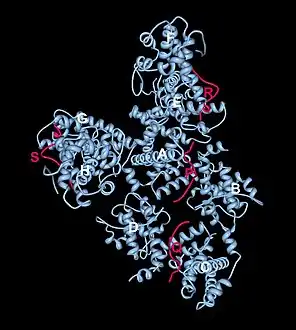

Crystal structure of the retinoblastoma tumor suppressor protein bound to E2F peptide polymer

Crystal structure of the retinoblastoma tumor suppressor protein bound to E2F peptide polymer